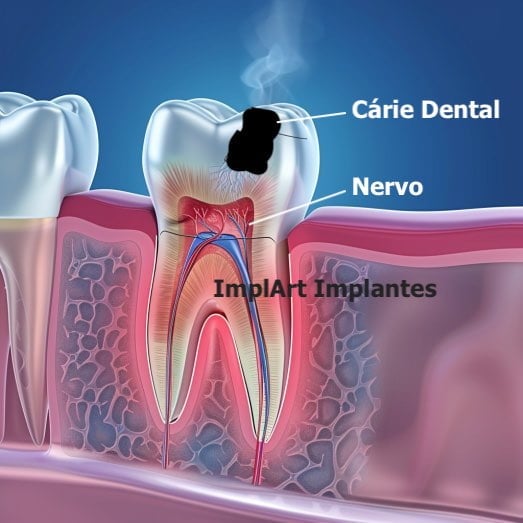

A Descoberta da Causa Raiz: Tudo começa com uma investigação minuciosa. O dentista usa radiografias para identificar a extensão do problema, como cáries profundas, fraturas ou traumas que levaram à inflamação ou infecção da polpa. É o primeiro passo para planejar a intervenção.

O Coração do Dente: A polpa dental é o tecido mole no interior do dente, que abriga nervos e vasos sanguíneos. Quando ela é afetada por cáries profundas, traumas ou infecções, o tratamento endodôntico se torna necessário para remover essa parte comprometida.